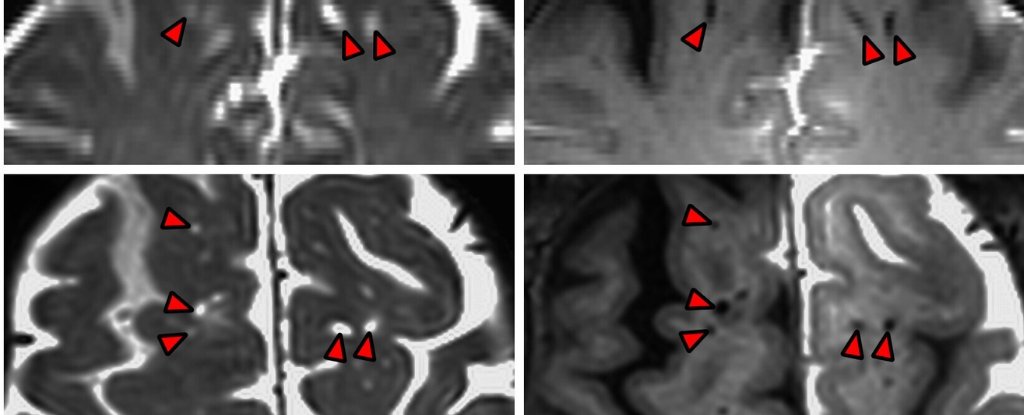

به گزارش ساینس‌الرت، مطابق پژوهشی که در PNAS انتشار شده است، در اعماق شکاف‌های پنج تکه مغز انسان، دانشمندان برای اولین بار پیچیدگی‌های یک شبکه لوله‌کشی زیربنایی را – که قبلاً در موش‌ها دیده شده و در گونه ما فقط فرضیه‌هایی را نقل کرده می بود – به عکس کشیدند.

قبل از این که CSF جانشین شود، دانشمندان آن را با یک ردیاب کنتراست تیره علامت‌گذاری کردند. بعداً، نوع خاصی از تصویربرداری رزونانس مغناطیسی، محل جریان مایع در مغز شرکت‌کنندگان را ترسیم کرد.

یافته‌ها حاکی از آن است که مغز انسان به طور اتفاقی مایع مغزی نخاعی را جذب نمی‌کند. در عوض، مایع با جستوجو‌کردن مسیر رگ‌های خونی عمیق‌تر به بافت عصبی نفوذ می‌کند.

این کانال‌های اشکار‌شده CSF در واقع در اطراف خارج رگ‌های خونی قرار گرفته‌اند. مرزهای این «فضاهای دور عروقی» (Perivascular Spaces) از سلول‌های مغزی راه اندازی شده‌اند که پایه‌های خود را به یکدیگر می‌چسبانند و یک مانع نفوذپذیر را راه اندازی خواهند داد.

«ارین یاماموتو»، حراج اعصاب OHSU می‌گوید می‌توان در تصاویر MRI حاضر در این پژوهش دید که فضاهای دور عروقی تیره در مغز به‌مرور زمان روشن خواهد شد. این فرایند تا حد بسیاری همانند فرایند مشاهده‌شده در مغز موش‌ها بوده است.